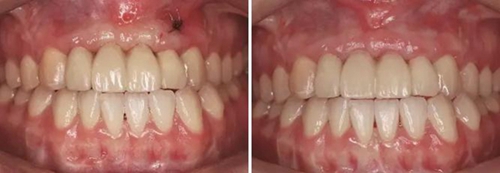

圖19 早期修復(fù)1月 圖20 早期修復(fù)2月

圖21 早期修復(fù)3月 圖22 早期修復(fù)3月打開三角間隙

圖23 早期修復(fù)4月 圖24 早期修復(fù)7月切除軟組織增生后

圖25 早期修復(fù)7月調(diào)改橋體部形態(tài)為卵圓形并高度拋光 圖26 早期修復(fù)8月

圖27 早期修復(fù)8月調(diào)改后 圖28 早期修復(fù)10月